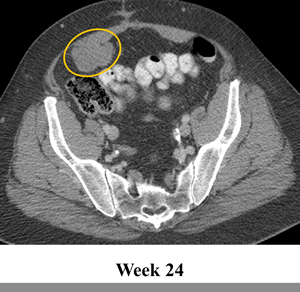

The patient was treated on a phase I trial of dabrafenib at a dose of 150 mg twice daily[10]. The patient’s baseline CT scan demonstrated multiple metastases in the lower abdomen and pelvis, with the largest tumors including a 6.3 cm mass posterior to the bladder and a 6.3 cm mass in the anterior pelvis (Figure 1, Panel A). Using the Response Evaluation Criteria in Solid Tumors (RECIST) 1.0, restaging scans revealed a 14%, 18% and 20% decrease after 6, 15 and 24 weeks of treatment, respectively. Figure 1 Panel B demonstrates response on CT scan at 24 weeks. In addition, the tumor demonstrated a marked decrease in contrast enhancement, a response criteria that has been validated in GIST[12].

Figure 1: Tumor regression of 20% observed in abdominal and pelvic tumors on computerized tomography (CT). CT scan at (a) baseline and after (b) 24 weeks of treatment with BRAF inhibitor dabrafenib (GSK2118436).